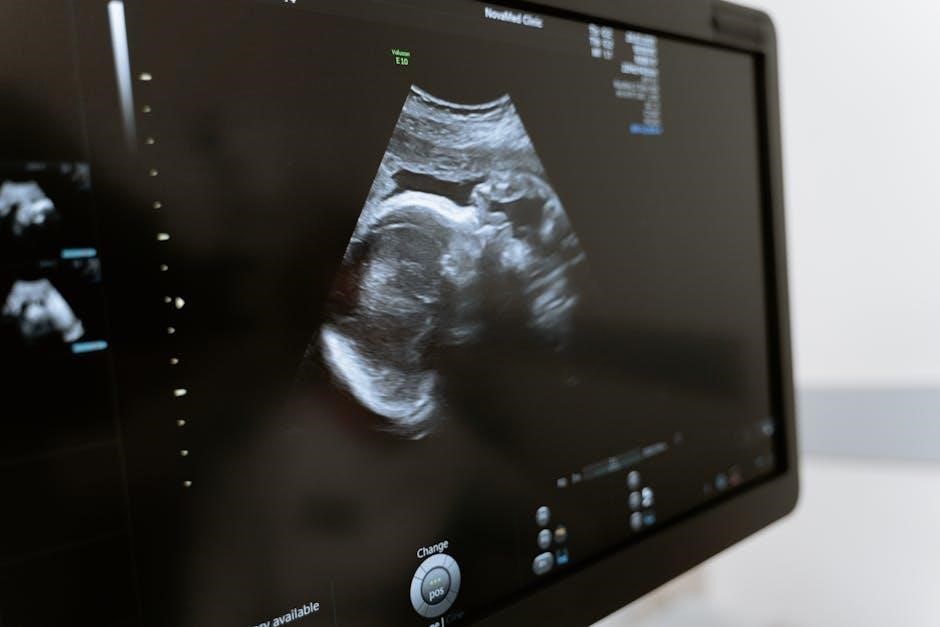

2.2 Image Guidance in Medical Procedures

Image guidance in medical procedures involves using real-time visualization to direct interventions accurately. Ultrasound is a key modality, offering dynamic, high-resolution imaging without radiation. Recent advancements, such as AI-powered systems from Laza Medical and robotic solutions from Mendaera, enhance precision. These technologies enable precise needle placement, tissue targeting, and minimally invasive techniques. For instance, DeepSight Technology’s NeedleVue LiteCart improves visualization during biopsies and anesthesia. Image guidance reduces complications, enhances safety, and improves outcomes, making it indispensable in modern medicine for procedures ranging from cancer treatment to regional anesthesia.